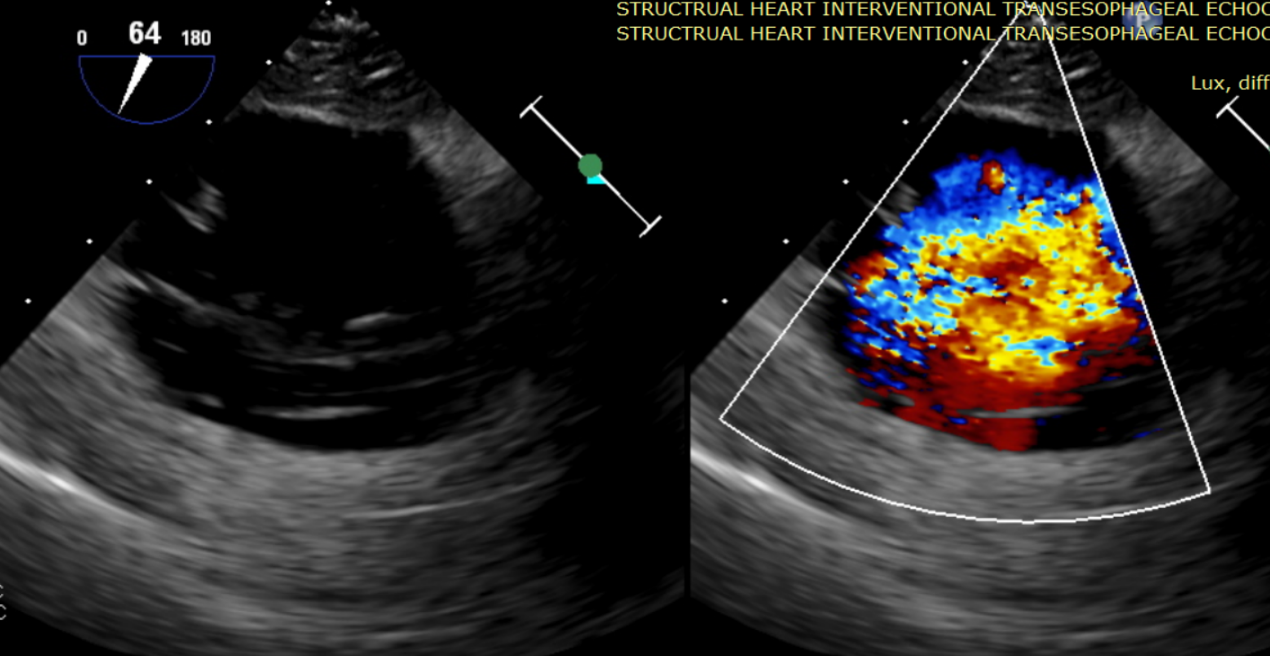

術(shù)中輸送器在超聲引導(dǎo)下調(diào)整位置